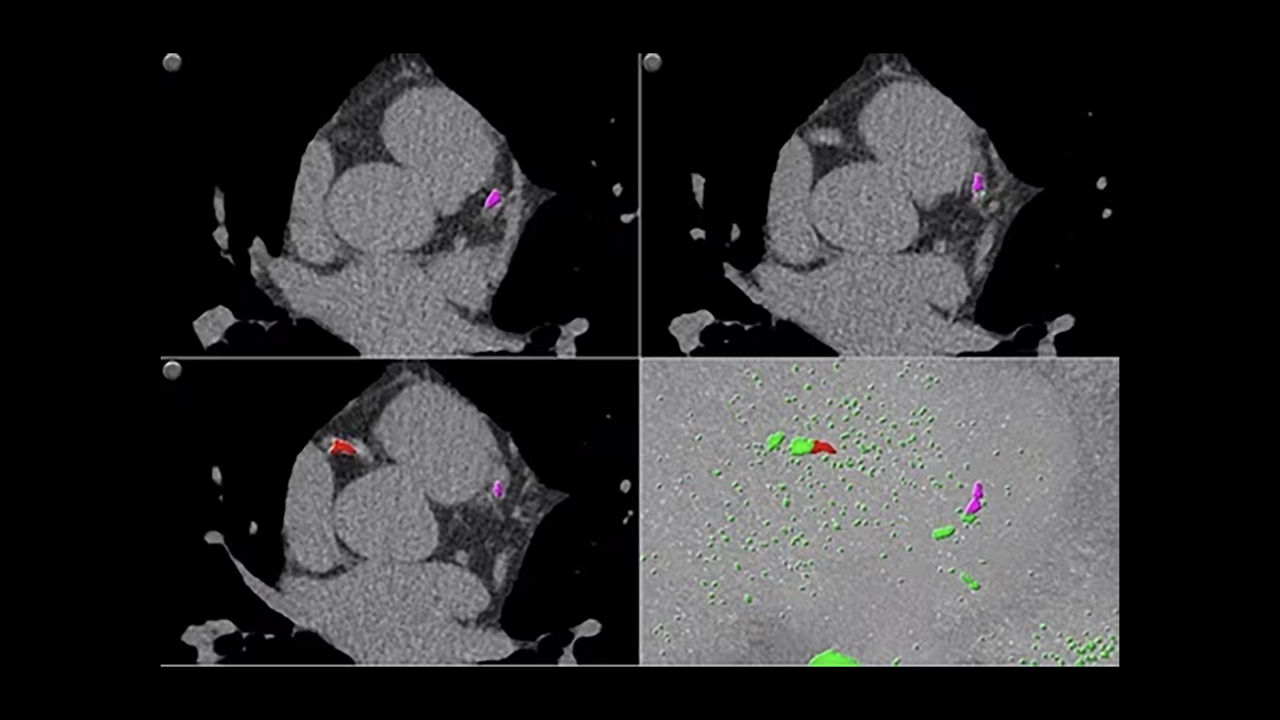

Automate Cardiac CT post processing and streamline your workflow.

<p>SnapShot Freeze 2</p>

<p>CardIQ Xpress 2.0 Reveal</p>

<p>SmartScore 4.0</p>